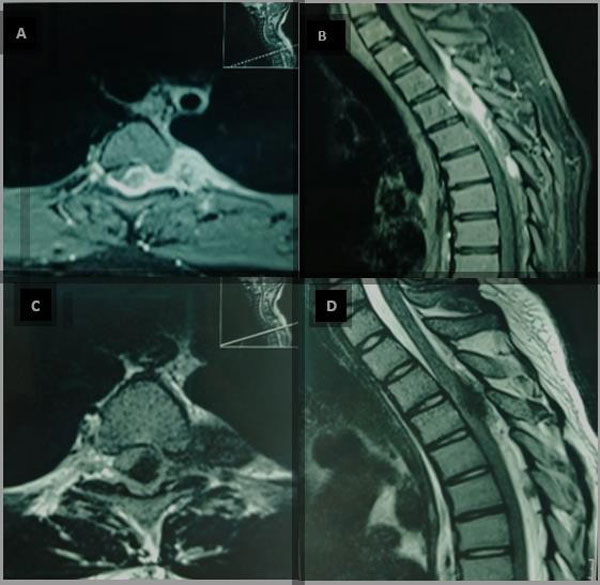

Durante su internación se realizaron estudios por imágenes. En la resonancia se evidenció tumor dorsal (D2-D5) de probable origen neurogénico localizado a nivel epidural que se extendía a la región paravertebral izquierda (Figura 1). En los estudios de laboratorio se encontró incremento de la velocidad de sedimentación globular, hemograma compatible con anemia microcítica e hipocrómica, ligera leucocitosis con neutrofilia. Marcadores tumorales, examen serológico y perfil autoinmune dentro de parámetros normales.

Figura 1. RM de columna dorsal. A y B) Con contraste. Evidencia lesión hipercaptadora homogénea que se extiende desde D2 – D6 con efecto de compresión medular extradural, principalmente a nivel de D3, con extensión a región paravertebral izquierda. C y D) En T2 se evidencia lesión hipointensa con efecto de compresión sobre médula espinal con extensión paravertebral izquierda hasta pleura parietal torácica.